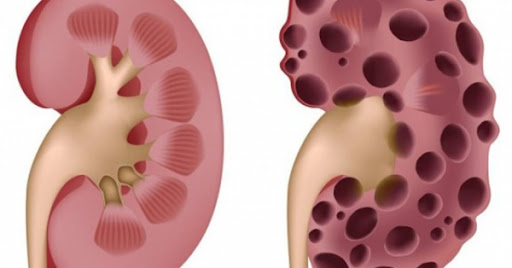

1. Suy thận

Suy thận là gì?

Bệnh suy thận cần được điều trị kịp thời tránh thận bị mất chức năng

Khi thận bị tổn thương thì sẽ dẫn đến giảm các chức năng của thận. Tùy theo thời gian thận bị tổn thương, bệnh suy thận có 2 nhóm chính: Suy thận mạn (bệnh thận mạn) và suy thận cấp (tổn thương thận cấp). Suy thận cấp là cấp độ nhẹ của bệnh suy thận, chỉ diễn ra trong vài ngày, có thể phục hồi một phần hoặc hoàn toàn chức năng thận sau khi được điều trị tích cực. Ngược lại, suy thận mạn nghiêm trọng hơn nhiều, không thể hồi phục hoàn toàn. Trong trường hợp này, biện pháp điều trị, can thiệp chỉ làm chậm và ngăn ngừa biến chứng của suy thận man. Lưu ý là khi chức năng thận giảm tới 90%, người bệnh phải điều trị bằng phương pháp chạy thận nhân tạo, thẩm phân phúc mạc hoặc ghép thận.